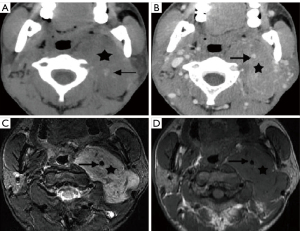

Secondary masses in the carotid space

Secondary masses refer to lesions that come from direct extension of diseases outside the carotid space. Primary head and neck malignancy can invade the carotid space directly, influencing staging and treatment (49). Some intracranial tumors may also extend into the carotid space through foramina and fissures of the skull base (50). Nasopharyngeal carcinomas can extend posterolaterally to involve the carotid space and form masses within it (51). When this process occurs submucosally, the lesion in the carotid space may be misinterpreted as a primary carotid space tumor (Figure 20) (52,53). Intracranial tumors, such as schwannoma and meningioma, may extend extracranially into the carotid space through the jugular foramen, hypoglossal canal, or fissures of the skull base (Figure 21) (54).